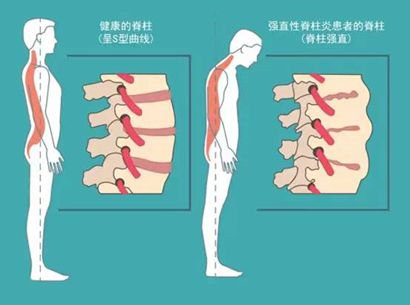

强直性脊柱炎(AS)是一种以骶髂关节和脊柱附着点炎症为主要特点的炎症性疾病,也被称为“不死的癌症”。与强直性脊柱炎有关的炎症因子一般最先侵犯骶髂关节,沿脊柱向上游走,在腰椎、胸椎、颈椎中不断衍生,摧毁椎体,让它们融合、畸形。

之所以称为“强直”,是因为该疾病进展到晚期会使关节融合在一起,失去活动性,脊柱就像“一根骨头”一样,无法弯曲。最后会出现脖子转不动、手臂抬不起、背也挺不直的状况。

最早为骶髂关节炎,后发展至腰骶部、胸椎及颈椎。早期病变处关节有炎性疼痛,伴关节周围肌肉痉挛,有僵硬感,晨起明显。也可表现为夜间疼,经活动或服止痛剂缓解。随着病情发展,关节疼痛减轻,而各脊柱段及关节活动受限和畸形,晚期整个脊柱和下肢变成僵硬的弓形,向前屈曲。